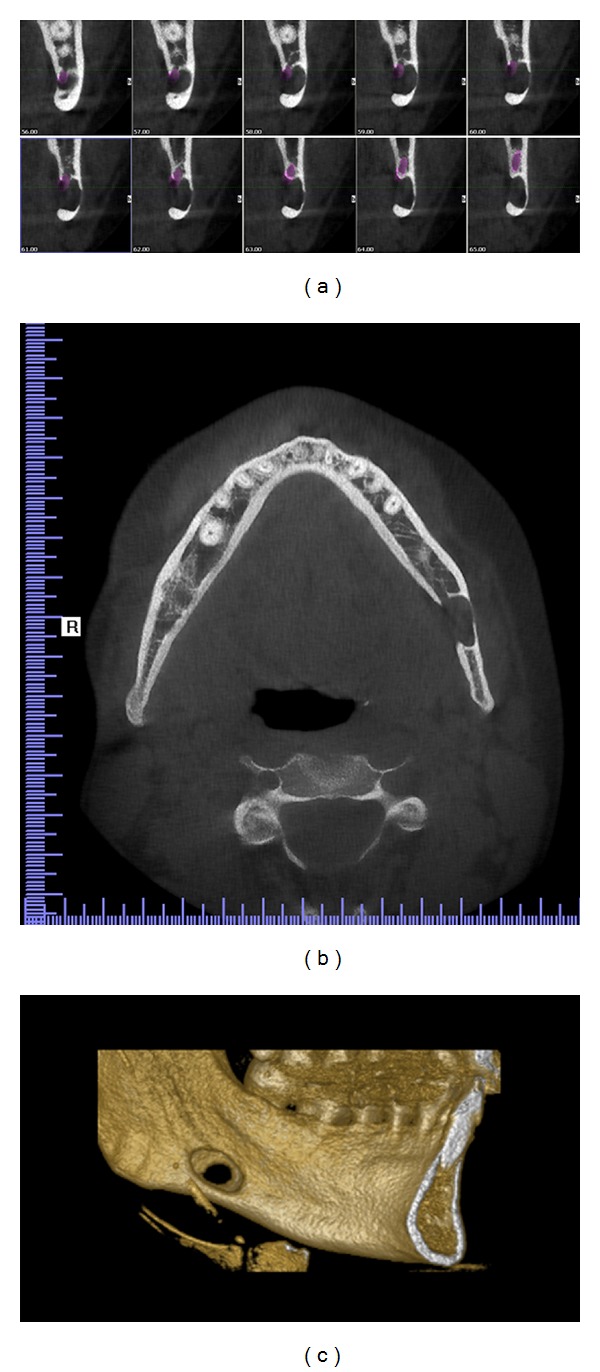

Figure 2.

CBCT images: (a) sagital view displaying continuous 1 mm width sections, (b) horizontal view displaying the cavity outline with diminished buccal cortical bone, and (c) 3D reconstruction of the left mandible displaying buccal cortical bone reduction.

A 31-year-old asymptomatic male patient was referred to Istanbul Medipol University, Faculty of Dentistry, Department of Dentomaxillofacial Radiology in order to undergo routine panoramic radiography. The patient was misdiagnosed in behalf of a cystic lesion of his left mandible by a former dentist. Medical history and dental history were not contributory. Palpation of the defect was not painful, and the cavity could be palpated by bidigital palpation. Cone beam computerized tomography (CBCT) was found appropriate for further evaluation (see Figures 2 and 4). Results showed an oval-shaped, radiolucent area of cystic aspect and regular, well-defined cortical outline with a little buccal cortical resorpton. Its longest axis was placed horizontally in the left hemimandible. This lithic area, located under the lower left second molar, was anterior to the mandibular angle. The lower wall of the mandibular canal which was visible within the radiolucent area showed that there could be a neighboring relationship, but not an involvement, of the inferior alveolar nerve (Figure 1). Patient displayed no pain or paresthesia. Lingual wall of the basal bone displayed involvement of the lesion and dimensions of the defect 14 × 10 × 6.4 mm depth (mesiodistal length, inferosuperior height, buccolingual depth).